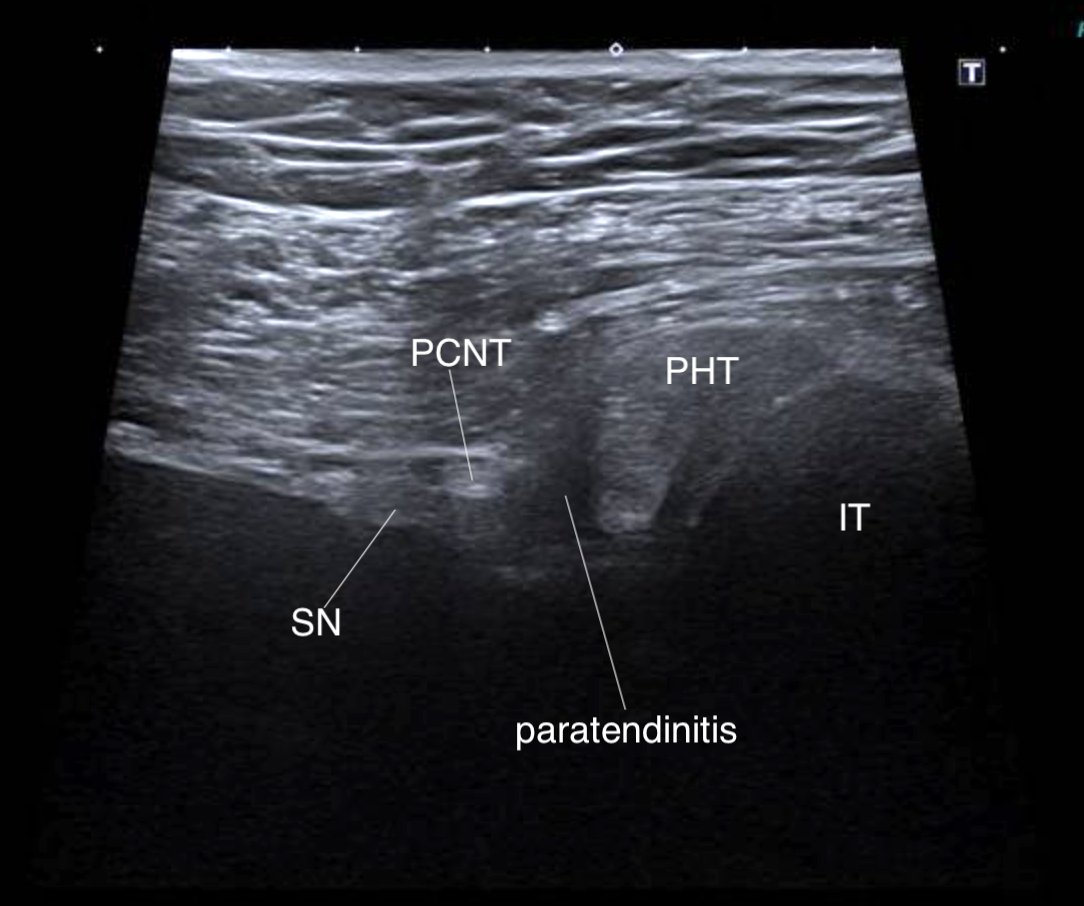

Happy to be part of the special #SportsImaging issue of Seminars in Musculoskeletal Radiology for #ESSR2025! Read our article on Sports-related Hip Injuries here: doi.org/10.1055/s-0045… #MSKrad Balgrist University Hospital Universität Zürich